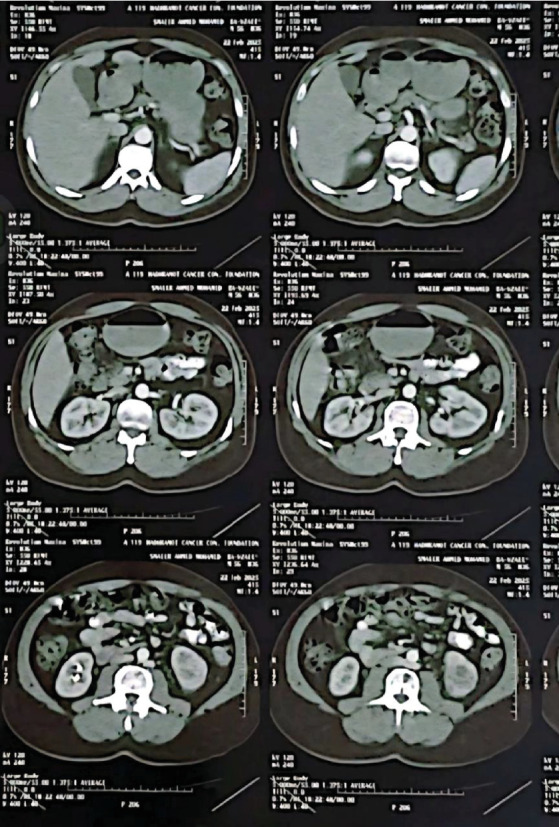

This case report describes a rare occurrence of a single isolated sacral metastasis in a 59-year-old male with clear cell renal cell carcinoma (ccRCC). The patient presented with progressive lower back pain and sacral numbness following a fall. Initial imaging revealed a destructive lytic lesion in the S1-S2 region and a left renal mass. A CT-guided biopsy of the sacral lesion confirmed metastatic ccRCC. PET-CT confirmed no additional metastases. Multidisciplinary management included partial left nephrectomy for the primary renal tumor, stereotactic body radiotherapy (SBRT; 45 Gy/15 fractions) targeting the sacral metastasis, and immunotherapy with sunitinib. The patient experienced significant pain relief within 1-week post radiotherapy and demonstrated stable disease with near-resolution of the sacral lesion at 3-month follow-up. At 12 months, imaging confirmed sustained disease stability. This case highlights the importance of considering metastatic RCC in patients with isolated sacral lesions, even in the absence of disseminated disease, and underscores the efficacy of combining localized ablation, radiotherapy, and targeted systemic therapy. Early diagnosis and a tailored multidisciplinary approach are critical for optimizing outcomes in such rare presentations.

本病例报告描述了一例59岁男性透明细胞肾细胞癌(ccRCC)罕见的单一孤立的骶骨转移。患者在跌倒后出现进行性腰痛和骶部麻木。初步影像学显示S1-S2区破坏性溶解性病变和左肾肿块。ct引导下的骶骨病变活检证实转移性ccRCC。PET-CT证实无其他转移。多学科治疗包括原发性肾肿瘤的左肾部分切除术,针对骶骨转移的立体定向放射治疗(SBRT; 45 Gy/15分数)和舒尼替尼免疫治疗。患者放疗后1周内疼痛明显缓解,3个月随访时病情稳定,骶骨病变接近消退。12个月时,影像学证实疾病持续稳定。该病例强调了在孤立性骶骨病变患者中考虑转移性RCC的重要性,即使在没有弥散性疾病的情况下,也强调了局部消融、放疗和靶向全身治疗联合治疗的有效性。早期诊断和量身定制的多学科方法对于优化此类罕见表现的结果至关重要。